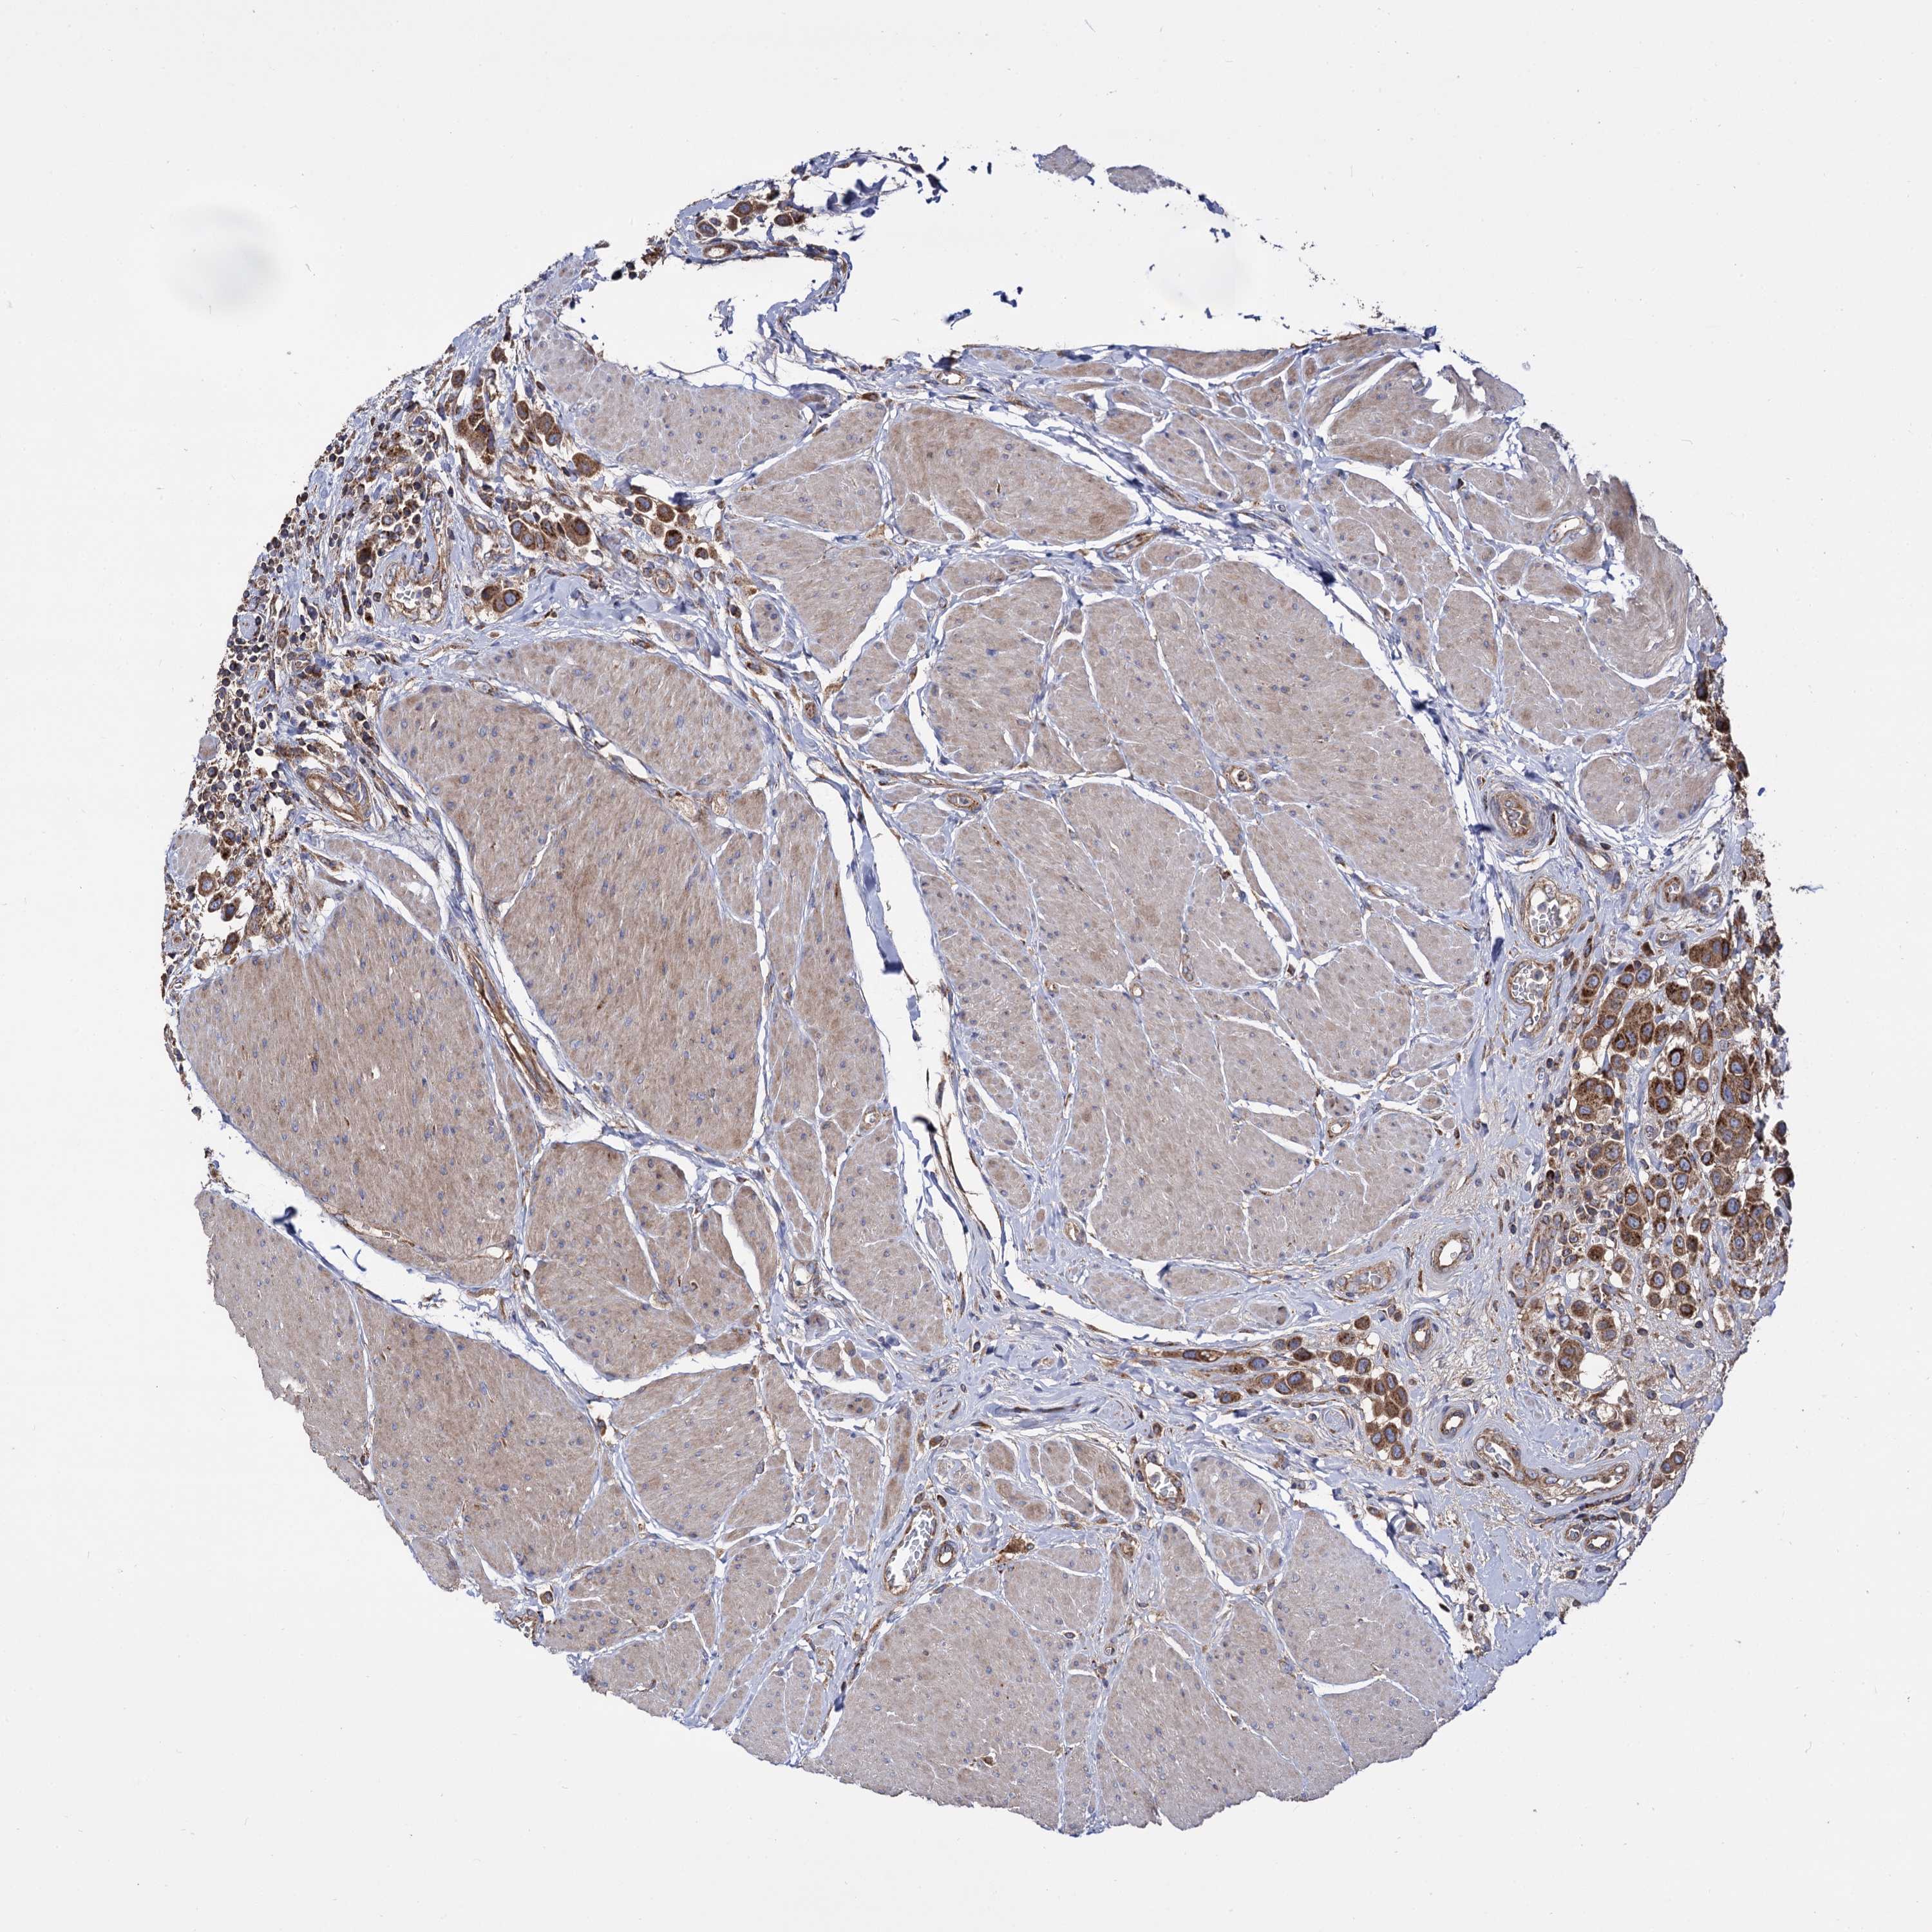

UROTHELIAL CANCER - Protein expressioni

A mouse-over function shows sample information and annotation data. Click on an image to view it in a full screen mode. Samples can be filtered based on level of antibody staining by selecting one or several of the following categories: high, medium, low and not detected. The assay and annotation is described here.

Note that samples used for immunohistochemistry by the Human Protein Atlas do not correspond to samples in the TCGA dataset.

Antibody stainingi

Antibody staining in the annotated cell types in the current human tissue is reported as not detected, low, medium, or high, based on conventional immunohistochemistry profiling in selected tissues. This score is based on the combination of the staining intensity and fraction of stained cells.

Each image is clickable and will lead to virtual microscopy that enables deeper exploration of all samples and also displays staining intensity scores, fraction scores and subcellular localization as well as patient and tissue information for each sample.

Antibody HPA040845

Staining

High

Medium

Low

Not detected

Intensity

Strong

Moderate

Weak

Negative

Quantity

>75%

75%-25%

<25%

None

Location

Nuclear

Cytoplasmic/membranous

Cytoplasmic/membranous,nuclear

Urothelial carcinoma, Low grade